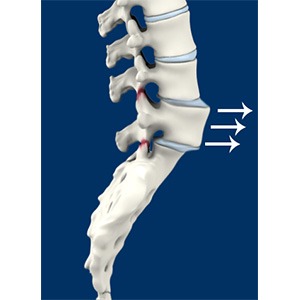

Spondylolisthesis

Spondylolisthesis is the displacement of the vertebral disc from the spinal column. Outward (forward) displacement is termed as anterolisthesis and inward (backward) displacement is termed as retrolisthesis. This condition is often preceded by spondylolysis, a degenerative condition of the vertebra.